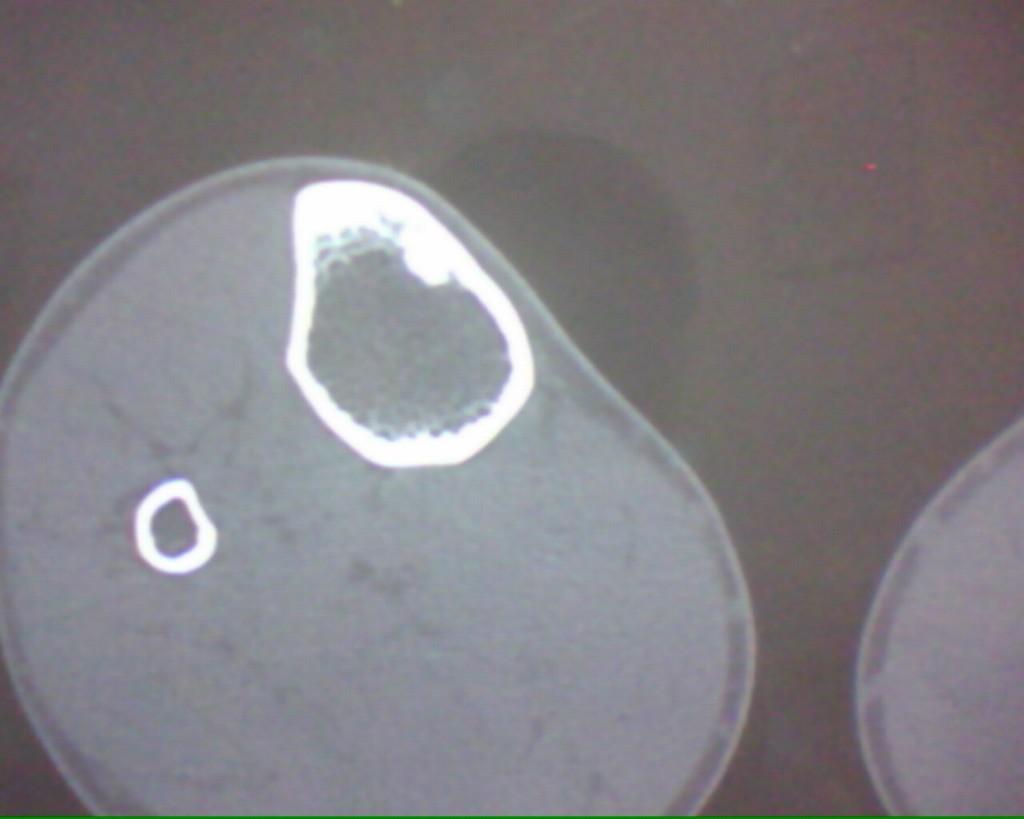

标题: CT19926:右胫骨上段高密度病变

男性,47岁,在一次外伤摄片中发现右胫骨上段条状高密度影,ct横断面上发现条状高密度影(钙化及骨化密度)位于胫骨皮质下,和皮质紧密相连,我考虑纤维性骨皮质缺损钙化可能性大,大家认为呢?大家注意看定位片,高密度病灶是很长的,横断面我只是选取了其中的几个层面。

这是一例经病理证实的纤维性骨皮质缺损钙化病例。

大家注意看定位片,高密度病灶是很长的,横断面我只是选取了其中的几个层面。